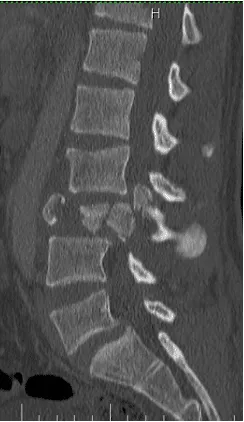

18 yo fell from 3 floors. Near complete loss of all neurological functions below the level of injury with near complete involvement of bowel and bladder

Patient was operated and the spinal canal cleaned up of all bony fragments. The spine was fixed from the side and the back to take care of instability.